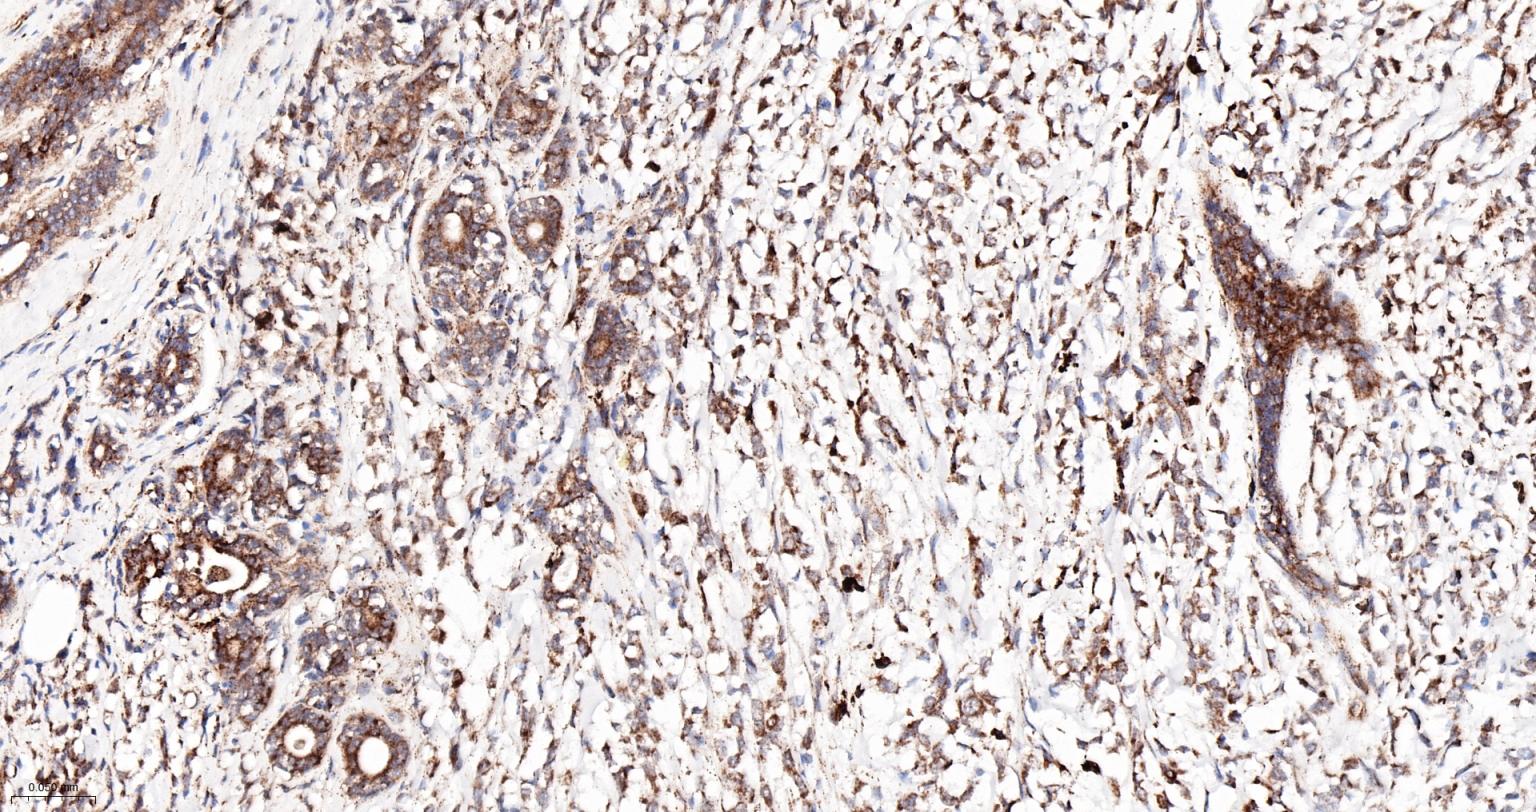

Paraformaldehyde-fixed, paraffin embedded Human Colon Cancer; Antigen retrieval by boiling in sodium citrate buffer (pH6.0) for 15 min; The section was incubated with AP2S1 Monoclonal Antibody, Unconjugated (bsm-61184R) at 1:200 overnight at 4°C, followed by conjugation to the bs-0295G-HRP and DAB (C-0010) staining.